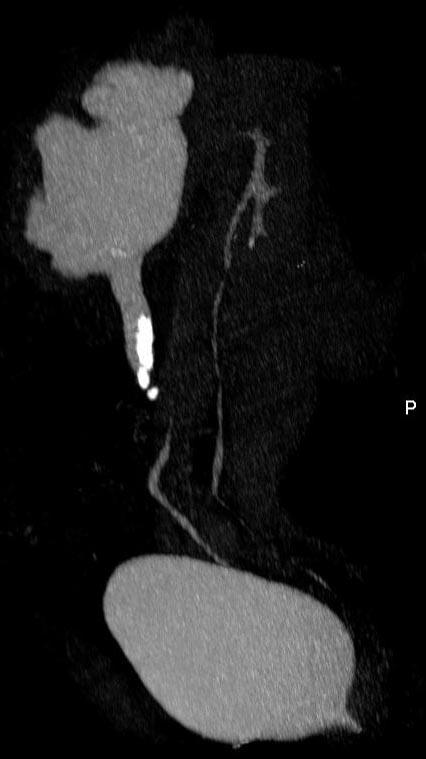

问题 男,42岁,反复左侧腰部疼痛伴血尿3个月余,CT检查如图,下列说法错误的是 ( )

选项 A、左输尿管结核并左肾积水 B、考虑为左输尿管结石并积水 C、左侧输尿管上段扩张 D、左侧肾盂肾盏扩张 E、左侧输尿管内可见多发的高密度影

答案 A